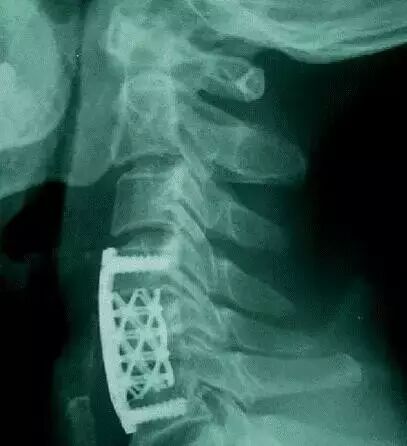

云女士罹患的恶性脊柱肿瘤累及4节颈椎。手术,预示着至少要切掉1节上颈椎3节下颈椎。这种大跨度的颈椎切除后椎体重建手术世界罕见。不应用3D打印技术,几乎成为无法完成的手术。

2016年10月17日,北京大学第三医院(以下简称「北医三院」)骨科主任刘忠军教授收治了一位4节颈椎被恶性肿瘤侵犯的重症患者。刘教授团队给患者实施了全世界首例4节颈椎切除手术,并给患者安装上全世界首个大跨度3D打印人工颈椎。

刘忠军教授团队在11月15日切除了癌症患者受肿瘤侵犯的四节颈椎后,给患者安装的,就是不具备再生功能的3D打印人体植入物。「这是世界首例四节颈椎切除手术,也是全世界首次用如此大跨度的3D打印内植物修复颈椎。做这么大跨度的颈椎切除,如果没有3D打印技术,我们现在是找不到合适的固定器械了。」刘忠军教授告诉奇点。

▲用来替换4节颈椎的3D打印内植物(是不是跟想象中的完全不一样,做成这样是有原因的,后文会告诉你)。该内植物通过两端的接头直接固定在第一节和第六节椎骨上。它的力学强度和与上下椎骨的接触面积,都明显大于传统的钛网。一段时间后,这个具备人体生理曲度的「海绵状」微孔钛合金3D打印内植物会被新生的骨组织充满(见下图),并被各种软组织包被。

在技术相对成熟的今天,定制3D打印内植物的过程并不复杂。首先给病人做CT扫描获取患者的颈椎数据,并用专业的软件把CT扫描的数据转换成3D打印的数据,然后就可以打印出患者的颈椎模型。医务人员再根据这个颈椎模型来设计内植物的大小,曲度和形态,然后把数据输入到相关的设备里面,只需开动机器打印就行了。按照目前的设备,打印这个替代4节椎骨的内植物大概需要13个小时左右。

奇点一直以为定制化3D打印椎骨跟人体的椎骨一模一样,然而并不是,而且完全不一样。后来奇点了解到,定制化3D打印椎骨之所以跟椎骨不一样,主要是考虑到实用性。由于颈椎中布满神经、血管和脊髓,所以为了便于手术中操作方便,在满足力学强度的前提下,就要把植入物设计的相对小一些。这样对患者的创伤也较小,更有利于患者快速恢复。

这个定制化3D打印椎骨最大的难点和亮点是通体「海绵状」的微孔结构。这就意味着整个内植物都是由微孔组成的。这样设计的目的主要是为了让人的骨头可以直接长到微孔里面,和这个内植物实现融合(7)。这也是跟钛网最主要的区别。